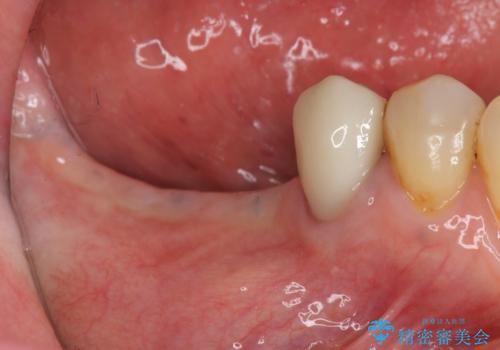

骨の造成を同時に行うインプラント治療

- 「長年使ってきた歯を失い入れ歯を入れてみたがよく噛めない、インプラント治療を受けたい。」とインプラントt利用を希望され来院されました。

骨は薄くなってしまい、インプラントの長期的な安定を見込むには不十分でしたのでインプラントの埋入と同時に周囲にコツの造成を行う治療計画を立てます。